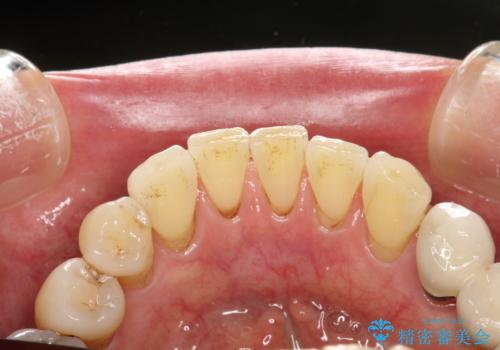

- 約2~3か月ごとに、定期的メンテナンスをしている方です。毎日紅茶をたくさん飲むとのことでステインを気にされ、クリーニング希望で来院されました。

全体的なチェックもかねてPMTC60分コースを行いました。

専門的な機械や材料を使用し、60分コースのPMTCクリーニングで、全体的な歯石や着色の除去を行いました。